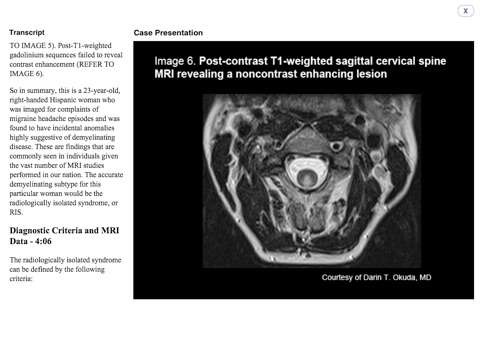

MedImage Cases(TM): Multiple Sclerosis, a new eTextbook, is a series of 26 biweekly MRI case presentations, providing audio commentary from renowned MS experts of the MRI—both conventional and non-conventional forms—to be used as a tool to measure disease activity, disease progression, and response to therapy, and guide practical therapeutic approaches. Clinicians can then translate this knowledge into successful personalized treatment strategies for patients with MS. Each case is peer reviewed and offers CME/CE credit to neurologists, IM specialists, family practice/PCPs, nurses and nurse practitioners, physician assistants and pharmacists who interact with and are involved in the management and treatment of patients with multiple sclerosis.